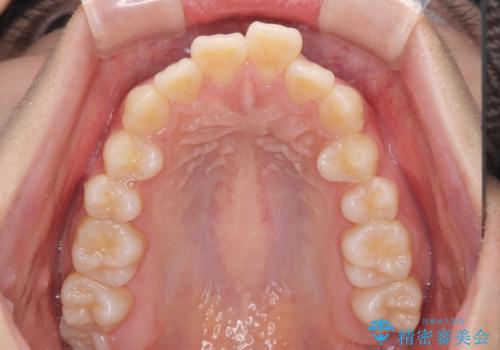

飛び出した上顎前歯 ワイヤー装置にて抜歯矯正治療

- 前に傾斜して飛び出した上顎前歯を気にして来院された患者様です。

上下前歯の前後差が大きく、下顎前歯が隠れるほど深い咬合で、咬合力が強い状態でした。

口元の突出感を改善するために、上下左右の第一小臼歯4本を抜歯し、ワイヤー装置にて矯正治療を行うこととしました。

深い咬み合わせの改善に時間がかかりましたが、下顎前歯がしっかりと見えるまでに整えることができ、口元の突出感も大幅に改善することができました。